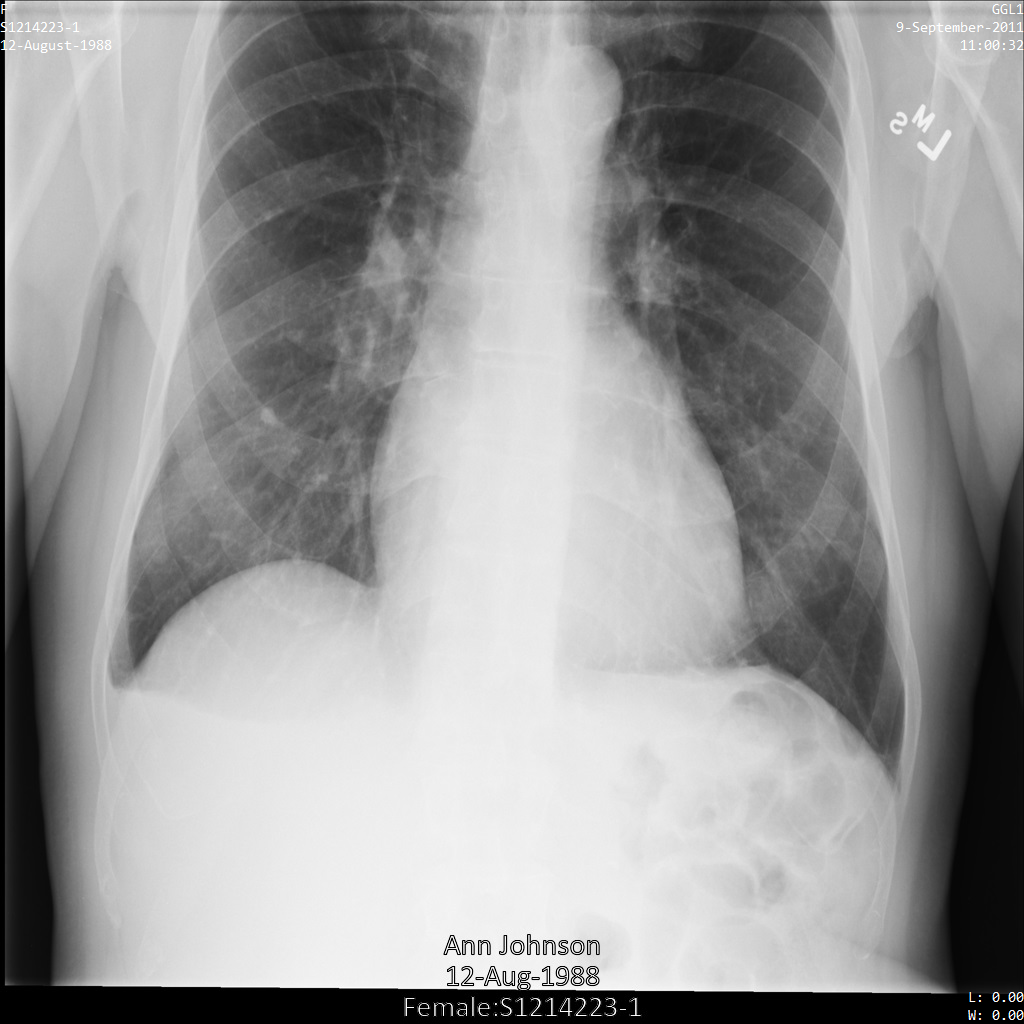

In jedem der folgenden Abschnitte finden Sie Beispiele zur De-Identifikation von DICOM-Daten mithilfe verschiedener Methoden. Für jedes Beispiel wird eine Ausgabe des de-identifizierten Images bereitgestellt. In jedem Beispiel wird das folgende Originalbild als Eingabe verwendet:

Sie können das Ausgabebild jedes De-Identifizierungsvorgangs mit diesem Originalbild vergleichen, um die Auswirkungen des Vorgangs zu sehen.

Nachdem Sie das Image an die Cloud Healthcare API gesendet haben, wird es wie folgt angezeigt. Während die Metadaten, die in den oberen Ecken des Bildes angezeigt werden, entfernt wurden, bleiben die eingebrannten geschützten Gesundheitsinformationen (PHI) unten im Bild erhalten. Informationen zum Entfernen des eingebrannten Texts finden Sie unter Eingebrannten Text aus Bildern entfernen.